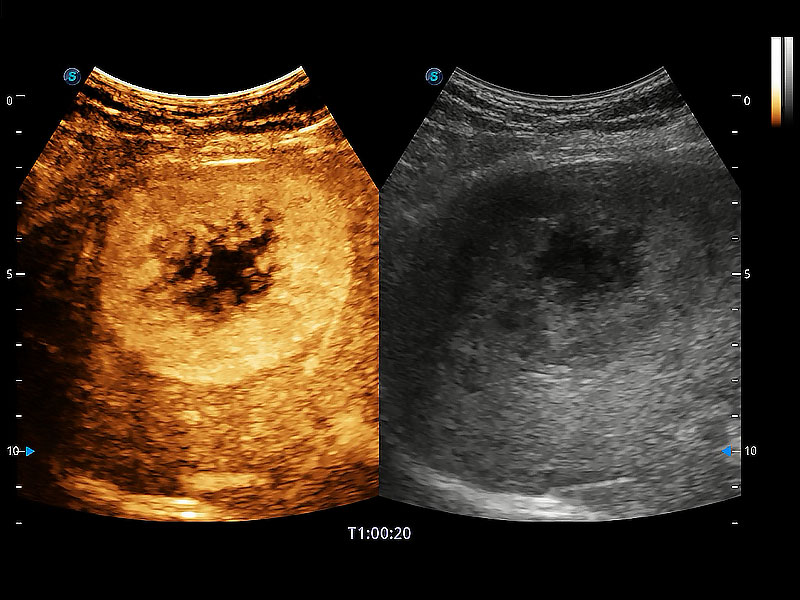

非线性融合造影成像充分利用谐波和基波信号,为难以观察的血流进行增强显像。可用于线阵、凸阵、微凸阵、相控阵探头。

为精细结构及组织边缘提供高清晰度的图像和更大的成像视野。帮助减轻医生的用眼疲劳,快速精准获得测量的数据。